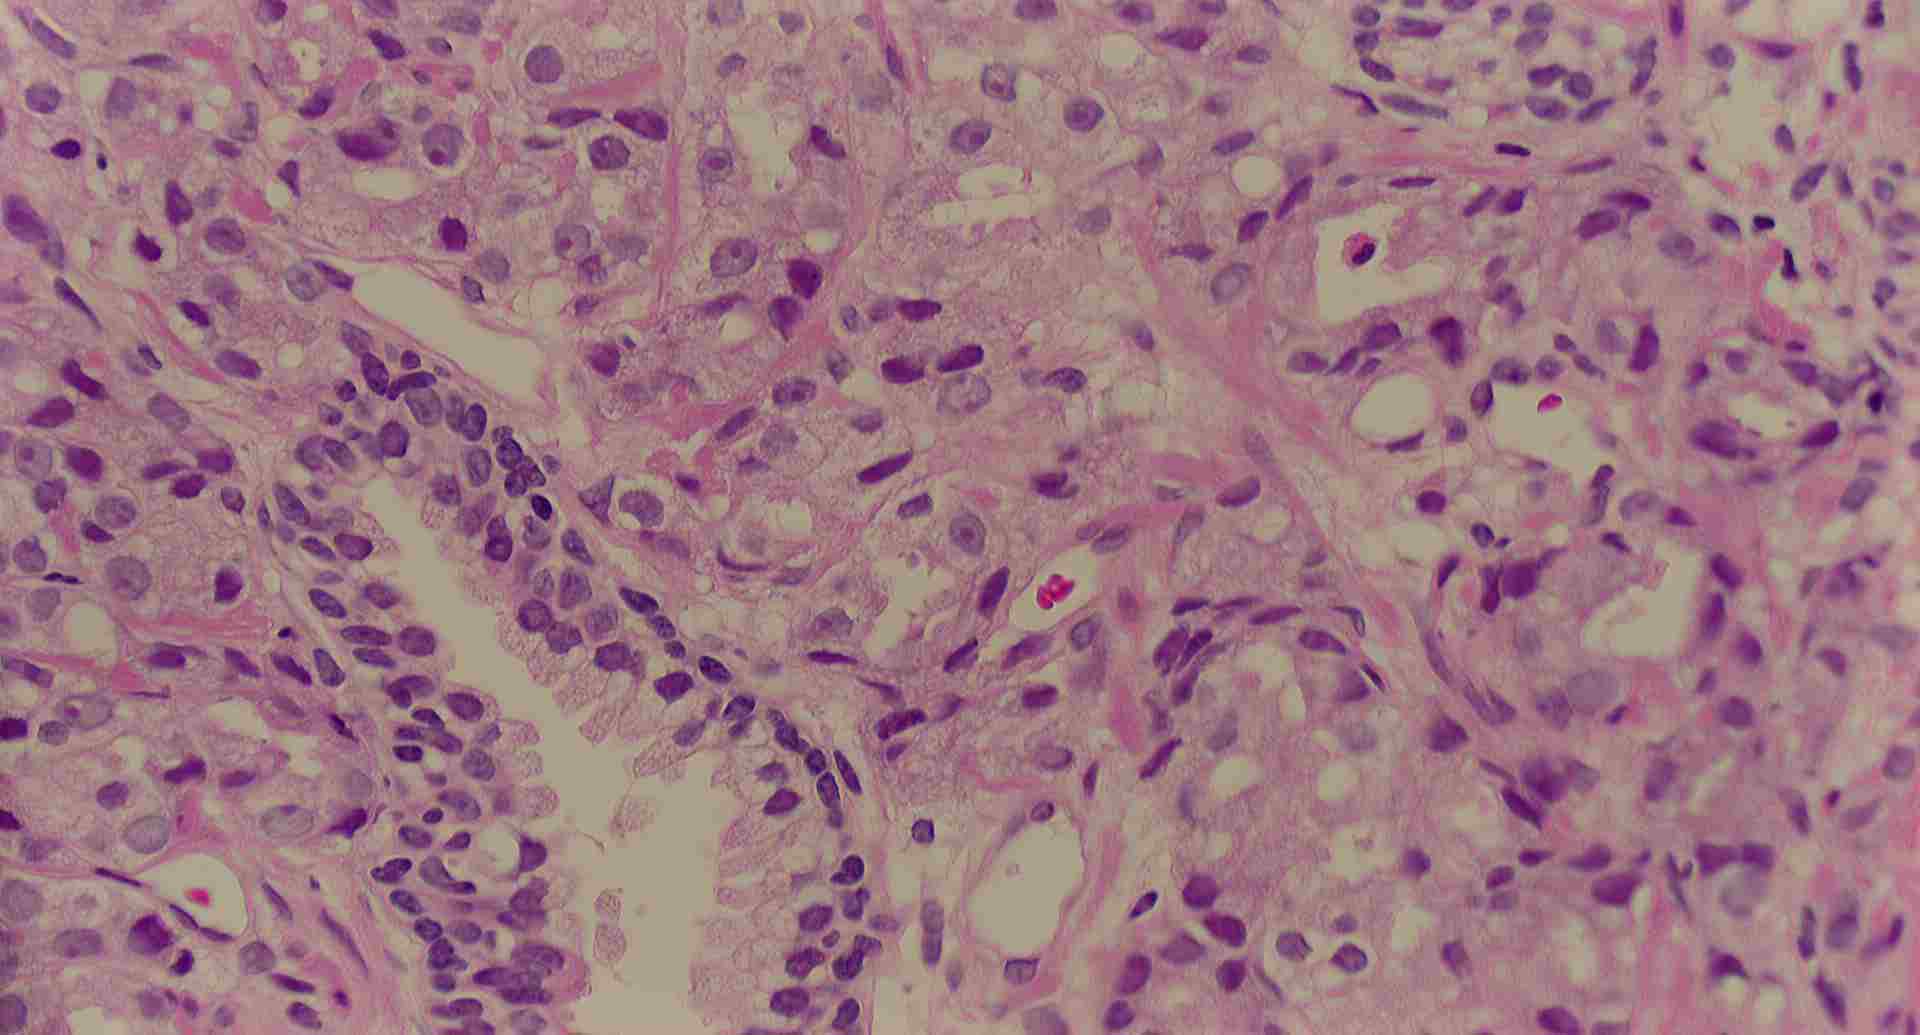

標本11